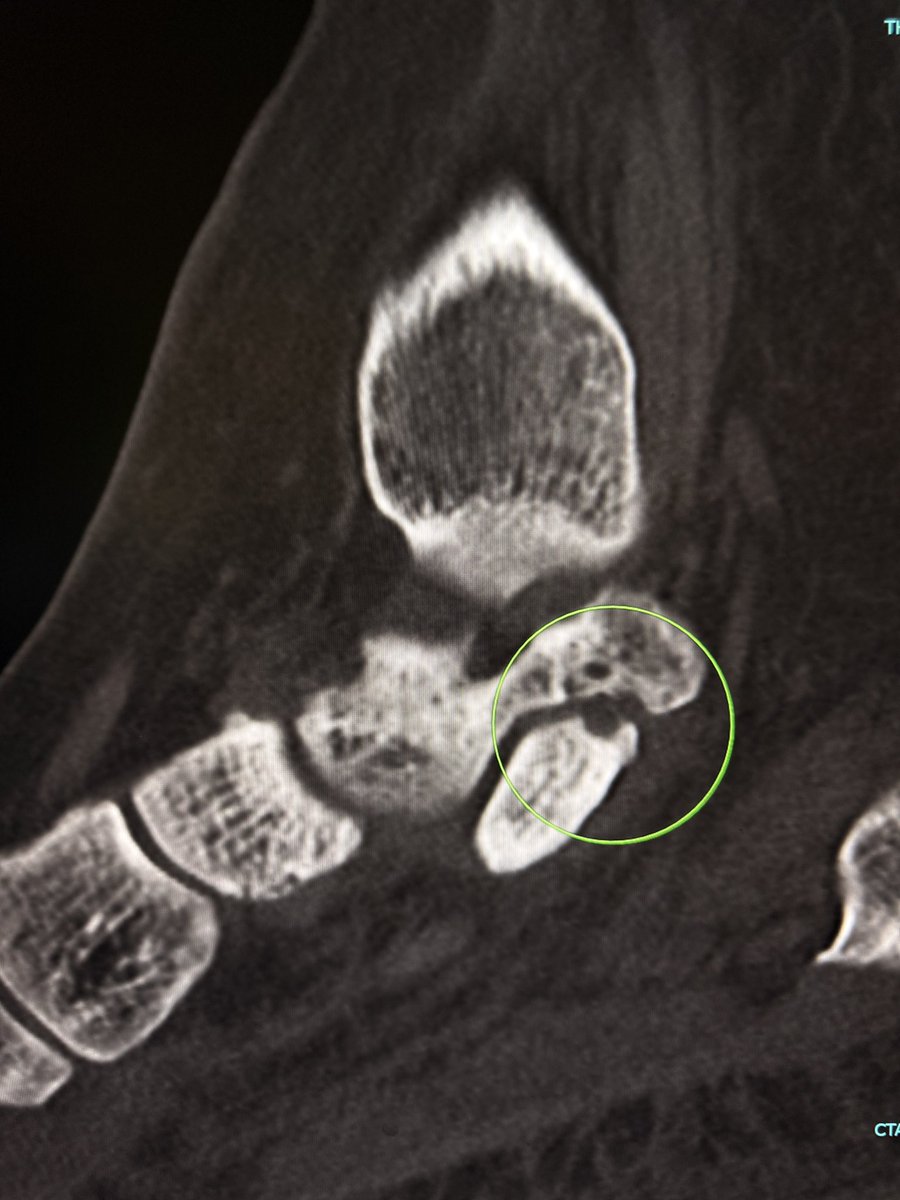

This case showed a fibrous coalition of Medial accessory talocalcaneal articulation at the level of the posterior sustentaculum tali, between the Talus and Calcaneus.

Wisdom: A talar beak should trigger a search, not end it.